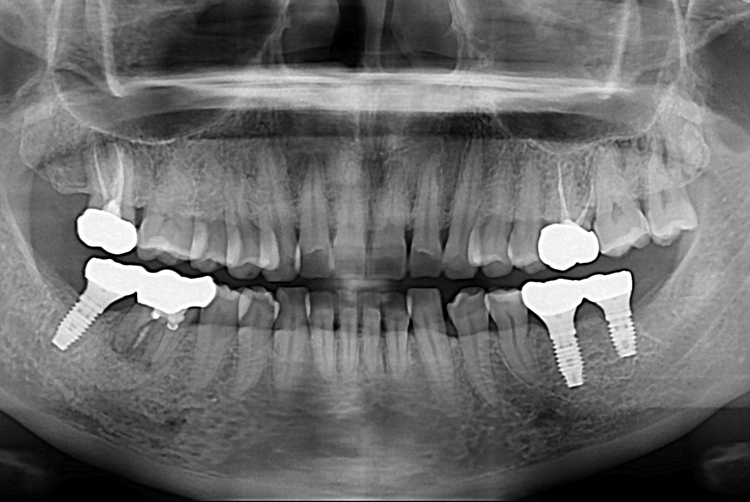

[임플란트] 어금니 임플란트

치료후 : 2017-12-15

세종치과는 많은 환자와 다양한 케이스를 바탕으로

항상 편안한 임플란트 수술을 제공하고자 노력하고,

오래동안 튼튼히 쓸 수 있는 임플란트 수술을 가장 큰 목표로 삼고 있습니다.